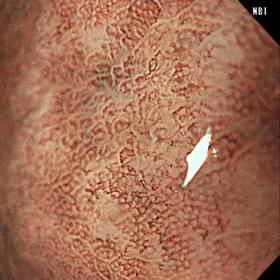

白色光通常観察の写真 NBI通常観察の写真 NBI拡大観察の写真

白色光通常観察 NBI通常観察 NBI拡大観察

(血管や粘膜の不整を認める)

早期胃癌(印環細胞癌)